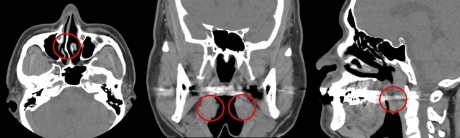

코골이를 진단하기 위해서는 호흡에 관여하는 코, 목, 편도 등에 관한 철저한 검사가 필요하다. 먼저 ▲코 안의 용종(물혹) ▲비중격 만곡증(코뼈가 휜 것) ▲만성 비염 ▲편도 비대증 ▲대설증(혀가 큰 것) 등과 같은 구조적 이상 유무를 확인한다. 이어 체중, 비만의 정도를 관찰하고 합병증과 관련 있는 고혈압, 부정맥 등 심혈관계에 대한 검사를 진행한다. 치료방침을 정하기 위해서는 내시경이나 X-ray, CT(컴퓨터단층촬영) 검사 등을 통해 폐쇄 부위를 정확히 확인하는 것이 중요하다.